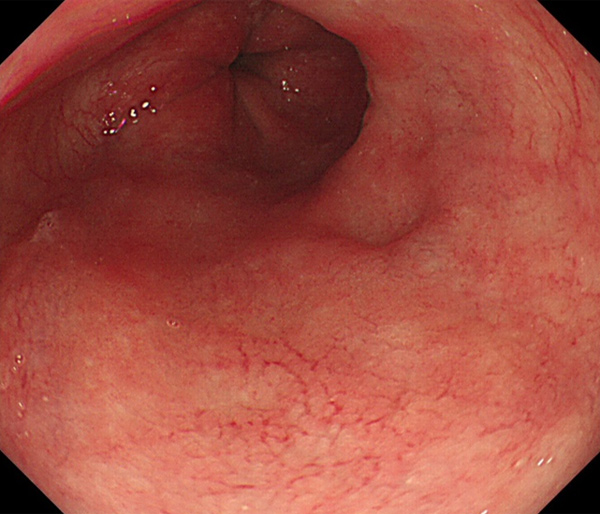

2026年1月24日開催の第19回研究会でご提示した検討症例です。 (画像をクリックすると拡大します)

2025年7月19日開催の第18回研究会でご提示した検討症例です。 (画像をクリックすると拡大します)

2025年1月11日開催の第17回研究会でご提示した検討症例です。 (画像をクリックすると拡大します)

2024年6月29日開催の第16回研究会でご提示した検討症例です。 (画像をクリックすると拡大します)

2024年1月6日開催の第15回研究会でご提示した検討症例です。 (画像をクリックすると拡大します)

2023年7月1日開催の第14回研究会でご提示した検討症例です。 (画像をクリックすると拡大します)

2023年1月21日開催の第13回研究会でご提示した検討症例です。 (画像をクリックすると拡大します)

2022年7月2日開催の第12回研究会でご提示した検討症例です。 (画像をクリックすると拡大します)

2022年1月22日開催の第11回研究会でご提示した検討症例です。 (画像をクリックすると拡大します)

2021年6月26日開催の第10回研究会でご提示した検討症例です。 (画像をクリックすると拡大します)

2021年1月23日開催の第9回研究会でご提示した検討症例です。 (画像をクリックすると拡大します)

2020年1月25日開催の第8回研究会でご提示した検討症例です。 (画像をクリックすると拡大します)

2019年1月12日開催の第6回研究会でご提示した検討症例です。 (画像をクリックすると拡大します)

2018年6月30日開催の第5回研究会でご提示した検討症例です。 (画像をクリックすると拡大します)

2017年7月15日開催の第3回研究会でご提示した検討症例です。 (画像をクリックすると拡大します)

2017年1月7日開催の第2回研究会でご提示した検討症例です。 (画像をクリックすると拡大します)

2016年6月4日開催の第1回研究会でご提示した検討症例です。 (画像をクリックすると拡大します)